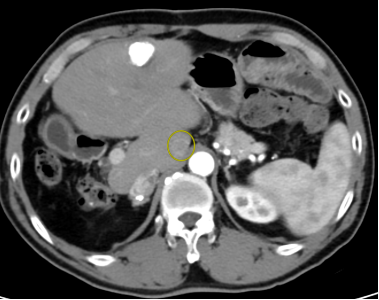

决定为王先生先行动脉介入化疗栓塞

治疗病灶的同时标记病灶

再行经皮穿刺无水酒精消融彻底毁损病灶

手术过程: